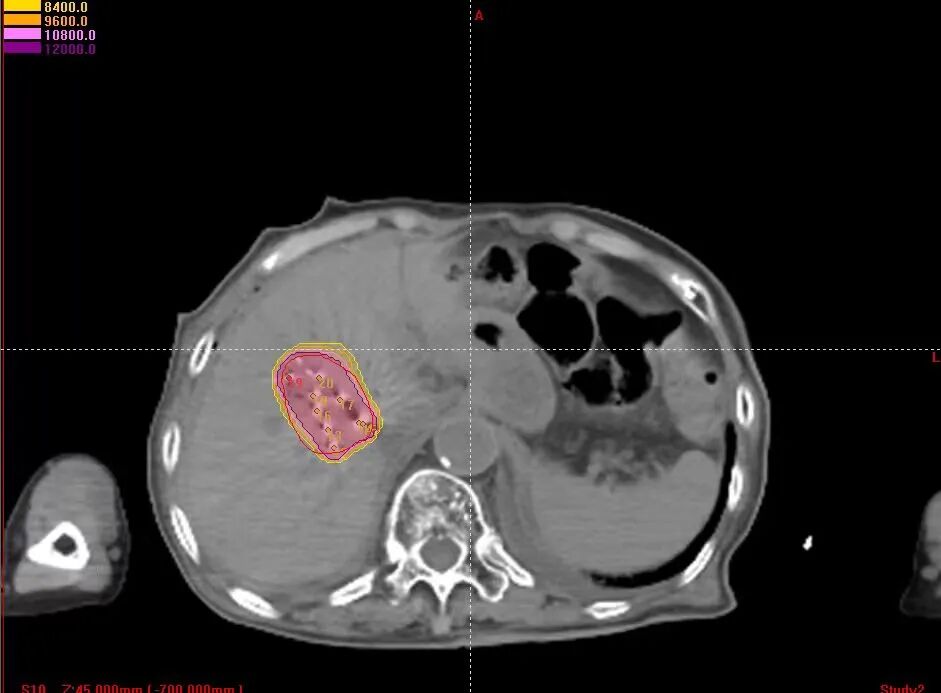

1、术前精准规划:制定三维治疗计划系统(TPS)勾画肿瘤靶区,精确规划粒子的分布范围、数量、活度及间距,确保粒子均匀覆盖整个病灶,同时避开周围的血管、胆管等正常组织,实现“局部剂量高、周围正常组织损伤小”的治疗目标。

2、术中精准引导:CT实时引导下,按3D打印模板预设粒子植入穿刺针道,术中避开大血管及胆管,实时CT扫描确认18G粒子植入穿刺针尖置于肿瘤远端预定位置后,采用退针法逐步植入碘125粒子,全程可视化操作,避免了传统手术中穿刺偏差导致的粒子分布不均或误损伤正常组织的风险。

3、术后精准验证:术后通过CT扫描重建粒子分布影像,显示碘125粒子均匀分布覆盖病灶,无冷区,与术前规划方案进行剂量对比验证,确保碘125粒子分布完全符合预设要求。